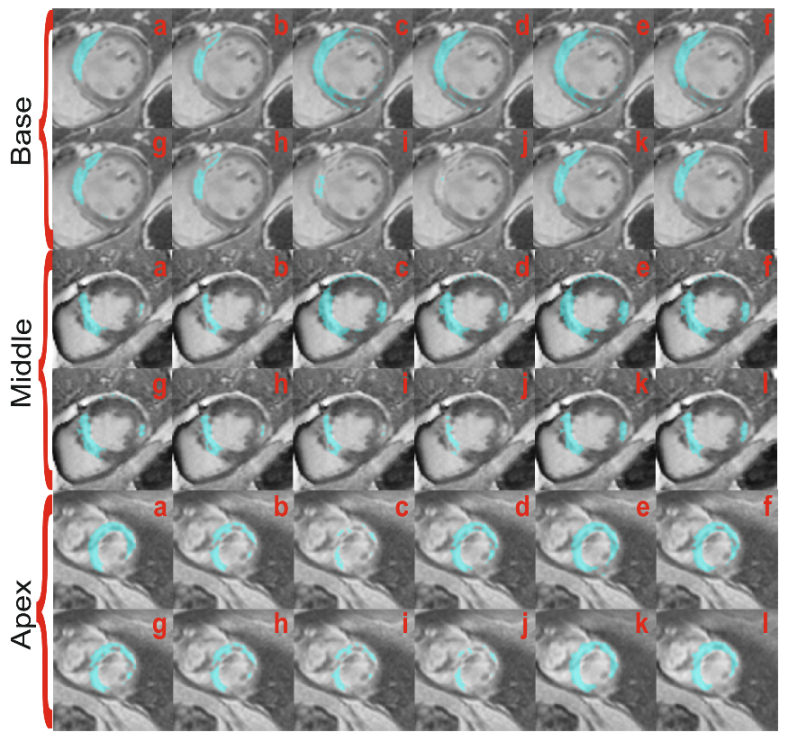

4.2.3. Microvascular Obstruction Inclusion